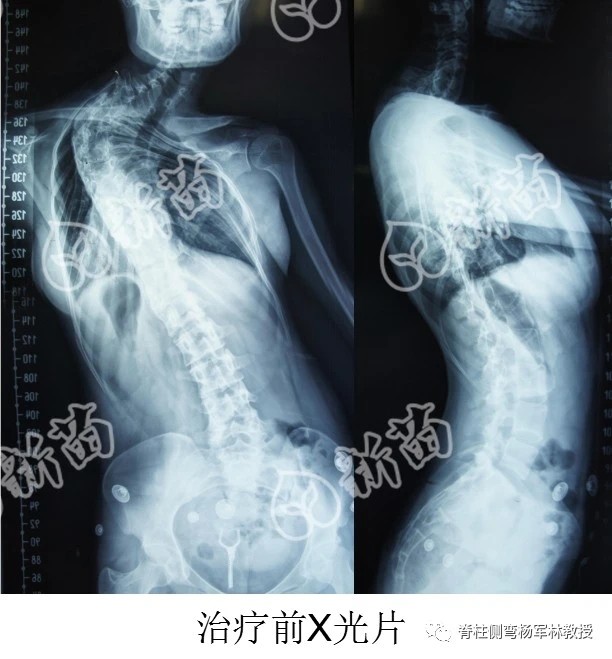

小琳曾经是位脊柱侧弯患者。在她上大一的时候,和父亲几乎走遍了全国所有医院,希望得到治疗,但均被告知手术后有90%的可能会瘫痪,没有一家医院愿意动手术。

2013年6月,在广东青基会新苗公益项目的资助下,小琳完成了手术。现在亭亭玉立的她,是一名人民教师。从绝望无助到即将毕业面对社会,她一腔孤勇,冒死也要做手术,重拾回人生的希望。

牵引的过程,痛苦又充满希望,等我的心肺功能达到手术指征后,我顺利躺在了杨军林教授主刀的手术台上。

据说手术中有诸多危险情况,但战果颇丰——外观矫正,心肺功能明显好转,奇妙的是,我还长高了将近十厘米!